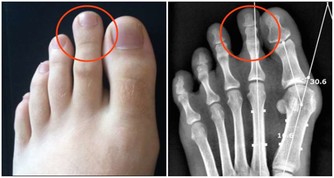

8. 強直性脊柱炎

強直性脊柱炎是一種影響脊柱的關節炎,會引起脊柱骨骼和脊柱與骨盆之間關節的炎症。症狀包括下背部和臀部疼痛與僵硬,它帶來的疼痛可能非常嚴重,以至於讓人徹夜不眠。